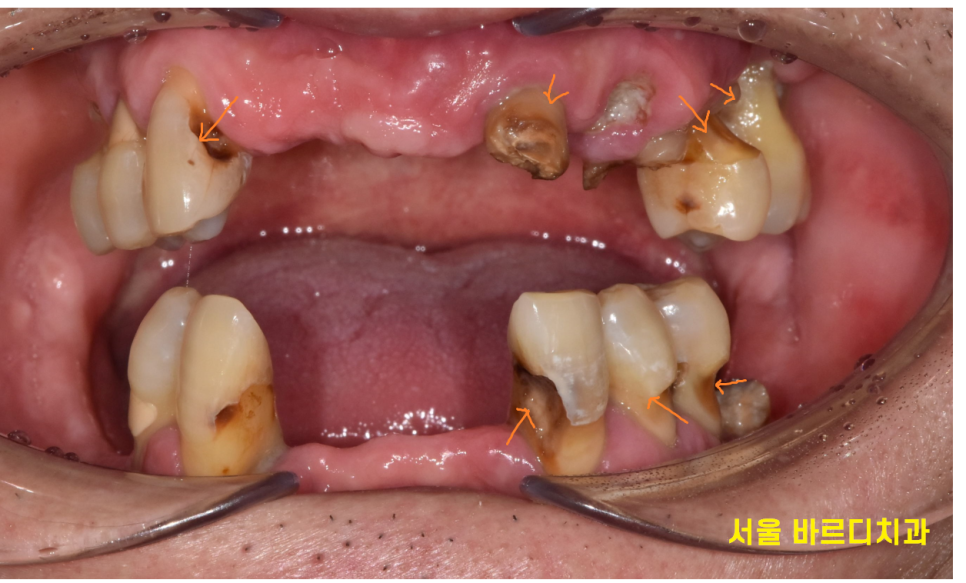

진료 전후 사진을 찍어 보여드리고 있습니다.

x-ray 사진은 환자분들께 설명을 드려도

좀더 직관적인 사진 활용을 많이 하고 있습니다.

사진 촬영도 결국 진단 과정중 일부인데요~

환자분 입 안 상태가 어땠드라..

사진을 통해 기억하기도 하고...

어쨌든 해석한 결과에 따라 치료 상담을 진행합니다.